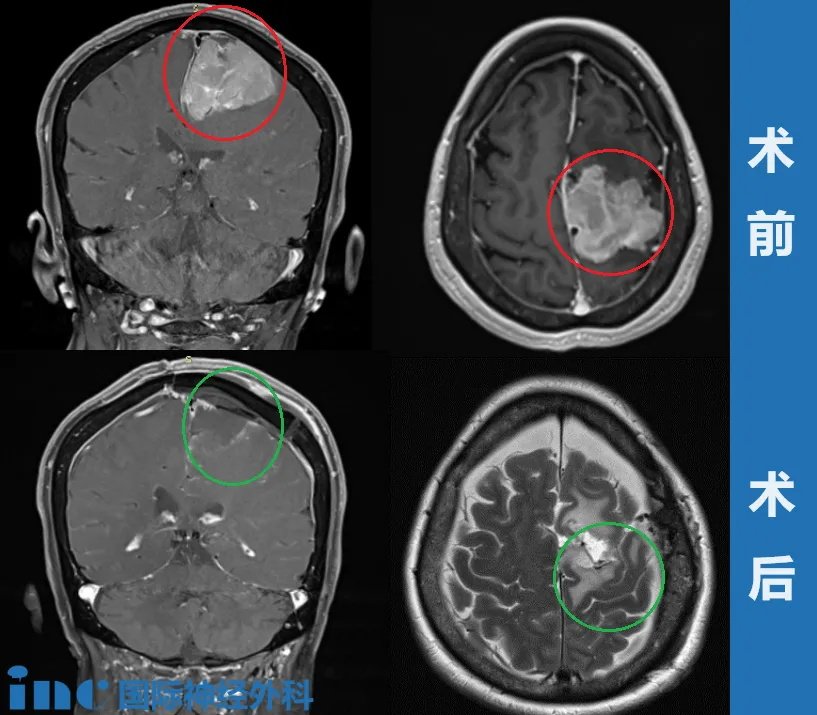

治疗过程:经过多次筛选和考量,王女士找到INC德国巴特朗菲教授。术前MRI显示左侧大脑镰旁巨大脑膜瘤,钙化和瘤周压迫、水肿效应明显。

手术过程——左侧额叶到额顶叶旁矢状面的成骨性环锯术和显微外科脑膜瘤切除术;自体骨膜移植的硬脑膜成形术。手术成功,肿瘤全切、矢状窦成功重建、运动功能区无损伤。术后影像显示肿瘤肉眼下全切,可见局部组织缺陷,水肿效应存在,被压迫正常脑组织缓慢复位。

▼术后5年CT影像